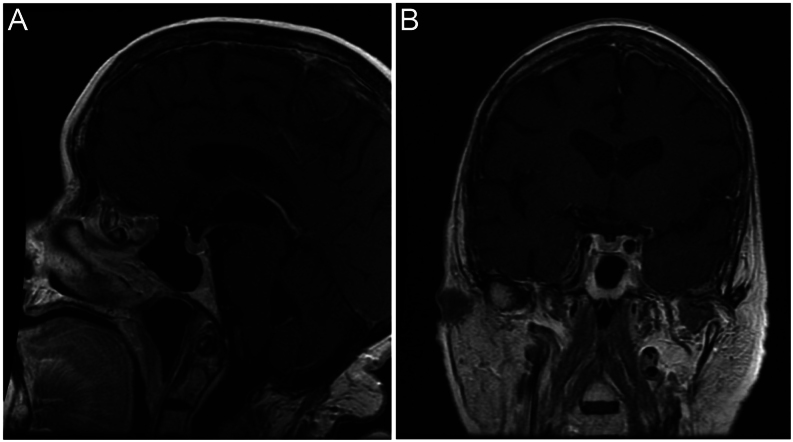

Summary: ACTH-secreting pituitary adenomas causing Cushing's disease (CD) typically present with weight gain, whereas weight loss and hypokalemia in endogenous Cushing's patients are suggestive of ectopic ACTH production. We report a case of CD presenting with atypical features of marked weight loss and hypokalemia. A 75-year-old female was admitted to the hospital with a history of profound weight loss, associated with uncontrolled hypertension, hyperglycemia, severe proximal muscle weakness, and hypokalemia. Subsequent investigations, including 24-h urinary free cortisol, 48-h low-dose dexamethasone suppression test, MRI of the sella, and bilateral inferior petrosal sinus sampling, confirmed CD without any evidence of ectopic ACTH production. She became eucortisolemic with medical therapy of ketoconazole and cabergoline, subsequently regained her weight, and became normokalemic. This case illustrates that patients with CD may present with symptoms and biochemical findings that would otherwise suggest ectopic ACTH production.

Learning points: Patients with CD do not always present with classical clinical features and may present with symptoms and biochemical findings that would otherwise suggest ectopic ACTH production. While most patients with CD typically lose weight after biochemical remission, some patients gain weight after the normalization of cortisol levels. This case highlights the need to entertain a broad differential in patients presenting with hypokalemia and weight loss and the need to exclude hypercortisolemia.